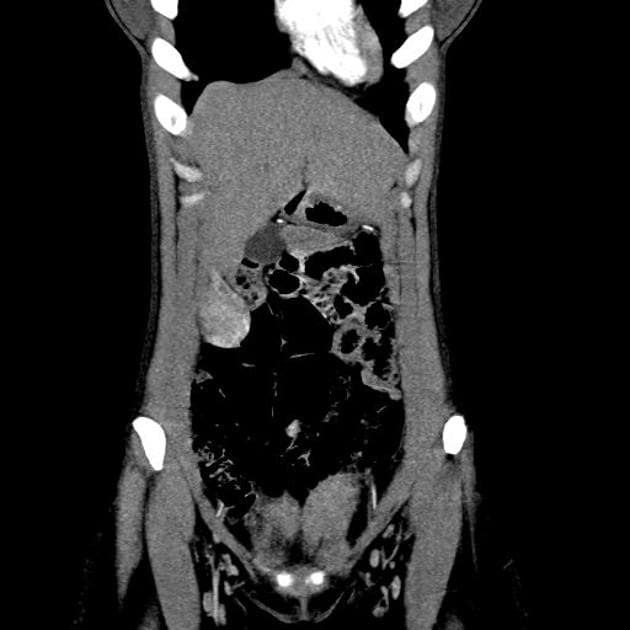

Một khối choán chỗ dưới gan giới hạn rõ được phát hiện trên siêu âm gần đây, trong quá trình đánh giá bệnh gan nhiễm mỡ ở bệnh nhân.

- Khối dạng lồi ra ngoài (exophytic) kích thước 58 × 38 mm, hình bầu dục, giới hạn rõ, tăng tưới máu (hypervascular), nằm ở phân đoạn gan thứ 3, trên hình ảnh cộng hưởng từ (MRI) cho thấy tăng quang đồng nhất sớm, không có hiện tượng washout trên các pha trễ.

- Không thấy dấu hiệu xâm lấn tại chỗ hoặc hạch bạch huyết vùng tăng kích thước.

- Giá trị cản quang gan không đồng nhất, thấp hơn lách, gợi ý gan nhiễm mỡ không đều.

Đây là trường hợp được xác định bằng giải phẫu bệnh là u tuyến gan (hepatocellular adenoma) – phân nhóm viêm (inflammatory subtype), đây là phân nhóm phổ biến nhất, thường gặp ở phụ nữ, hay liên quan đến béo phì, hội chứng chuyển hóa và gan nhiễm mỡ, và điển hình là tăng quang động mạch mạnh, không phải dạng viền, với giữ thuốc kéo dài trên các pha cửa và pha trễ.

U tuyến gan phát triển ra ngoài (exophytic hepatocellular adenoma)